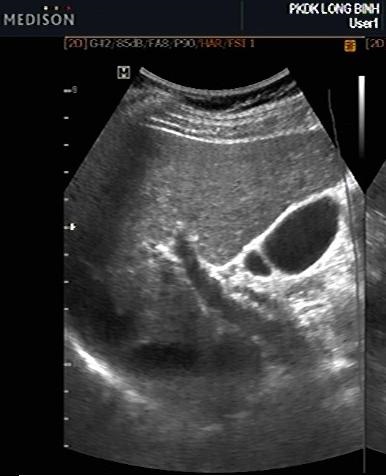

Image echographique normale

du foie droit en coupe intercostale de

la ligne axilaire anterieuse droit ( long sagitale -

vesiculaire ) . On en

voyait foie droit , branche droit de la veine porte

, vesicule biliaire et artere hepatique |

Coupe

transverse recurrent bifurcation portal et vesicule

biliaire . Le foie droit ,la vesicule biliaire , la

bifurcation de la veine porte et canal choledoque ,

artere hepatique peut en voyait sur cette coupe |